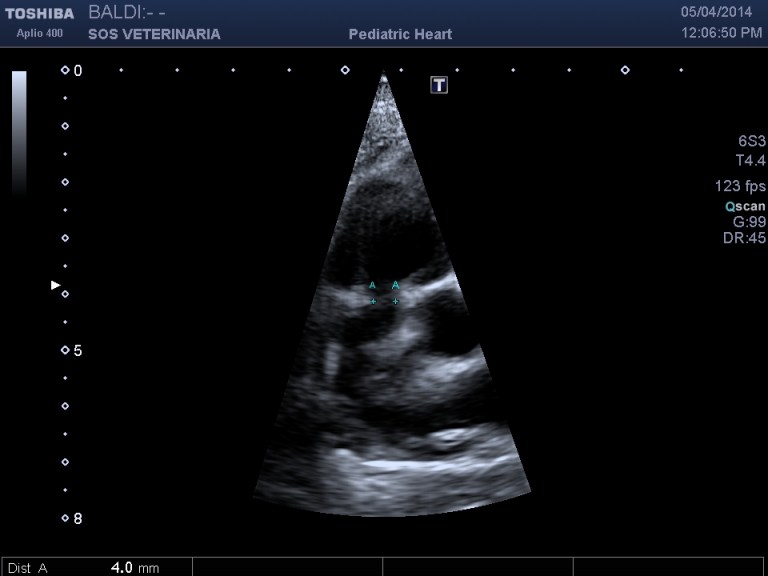

parasternale destra asse corto zoom

Questo Buldog di nome Ettore e’ stato presentato alla visita con soffio sistolico all’eta’ di tre mesi ed episodi di broncopolmonite ricorrente scarsamente responsiva alla terapia ,dall’esame ecocardiografico a mio avviso rientra in una diagnosi di anomalia della coronaria destra ed e’ stato deciso solo per il trattamento con beta bloccanti .

- imponente il grado di ipertrofia concentrica ventricolare destra con gradienti molto elevati superiori ai 100 mmHg (anche 160mmHg),il cuore ha subito fin da subito un necessario rimodellamento alla condizione

- L’anello stenotico e’ sempre piccolo

- difficilmente si visualizzano i lembi valvolari in quanto il restringimento dell’anulus generato dal passaggio della coronaria impedisce la loro apertura ,in transtoracica si possono visualizzare dritti come canne al vento

- nelle scansioni in cui si intravedono i lembi valvolari nessun effetto doming appare visualizzabile( come nella stenosi polmonare classica di tipo A)

- invece di lembi valvolari si visualizza un cordoncino simil fibroso il diametro della stenosi e’ sempre piccolo